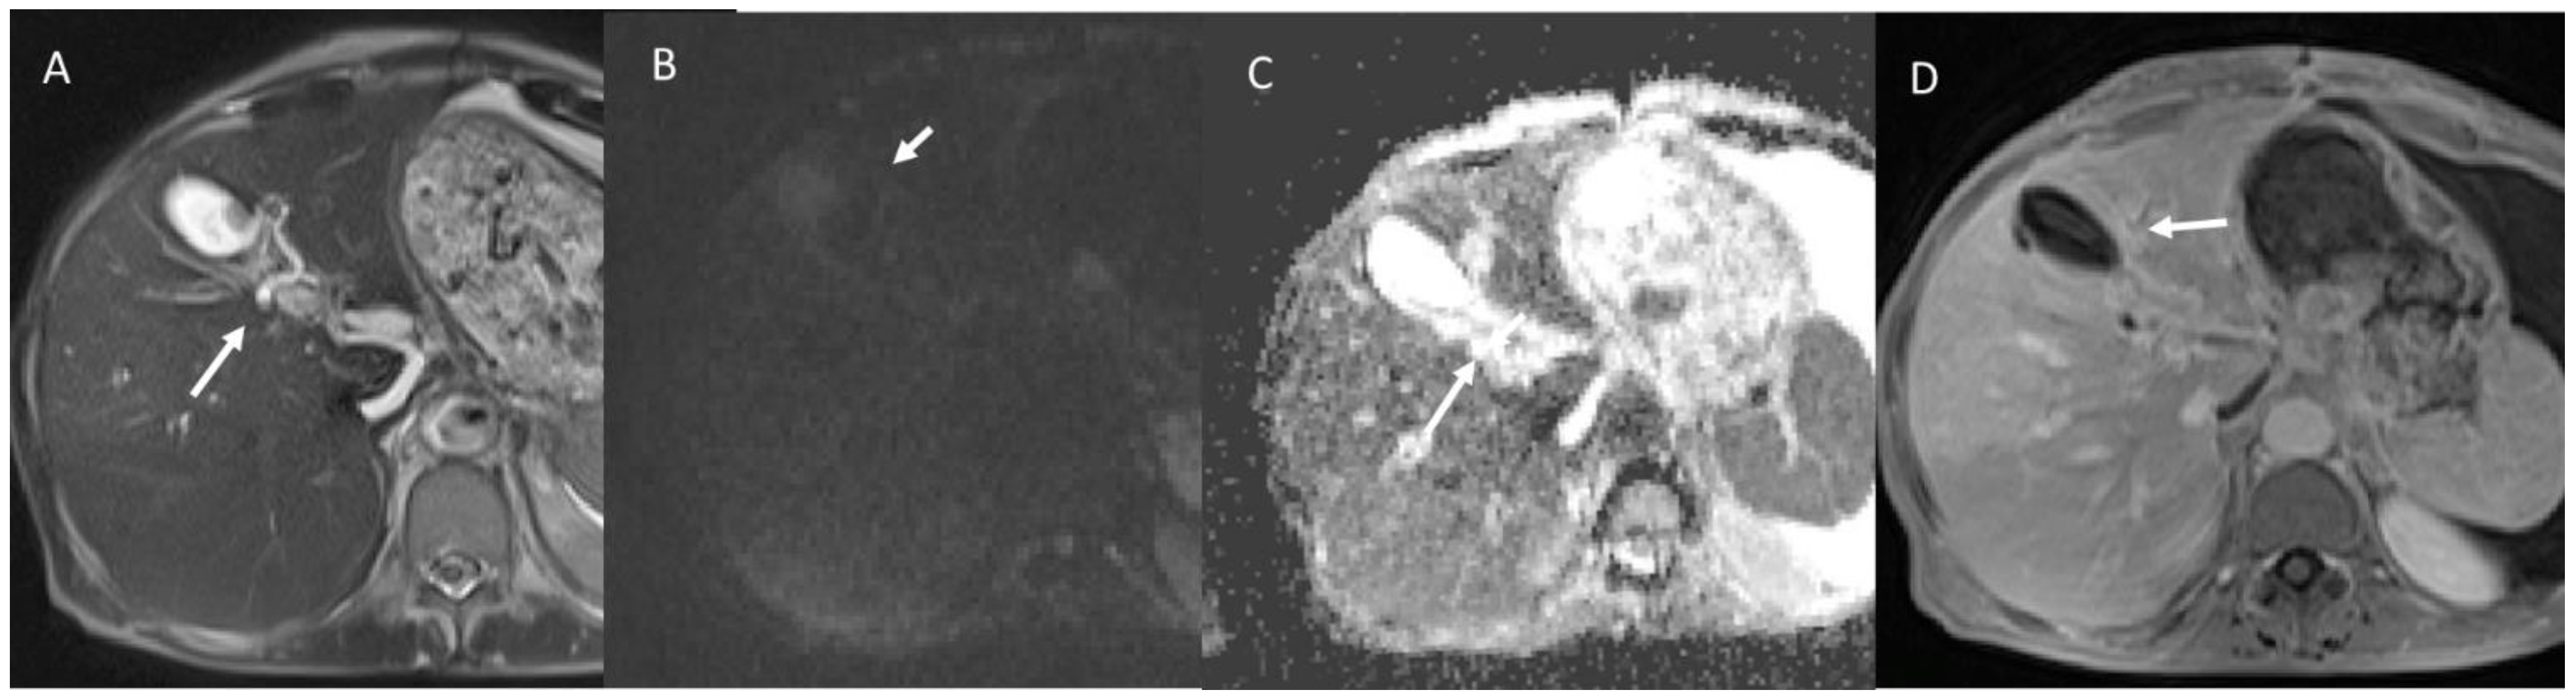

6.5. Diagnostic Management

- Granata, V.; Grassi, R.; Fusco, R.; Setola, S.V.; Belli, A.; Ottaiano, A.; Nasti, G.; La Porta, M.; Danti, G.; Cappabianca, S.; et al. Intrahepatic cholangiocarcinoma and its differential diagnosis at MRI: How radiologist should assess MR features. Radiol. Med. 2021, 126, 1584–1600. [Google Scholar] [CrossRef]